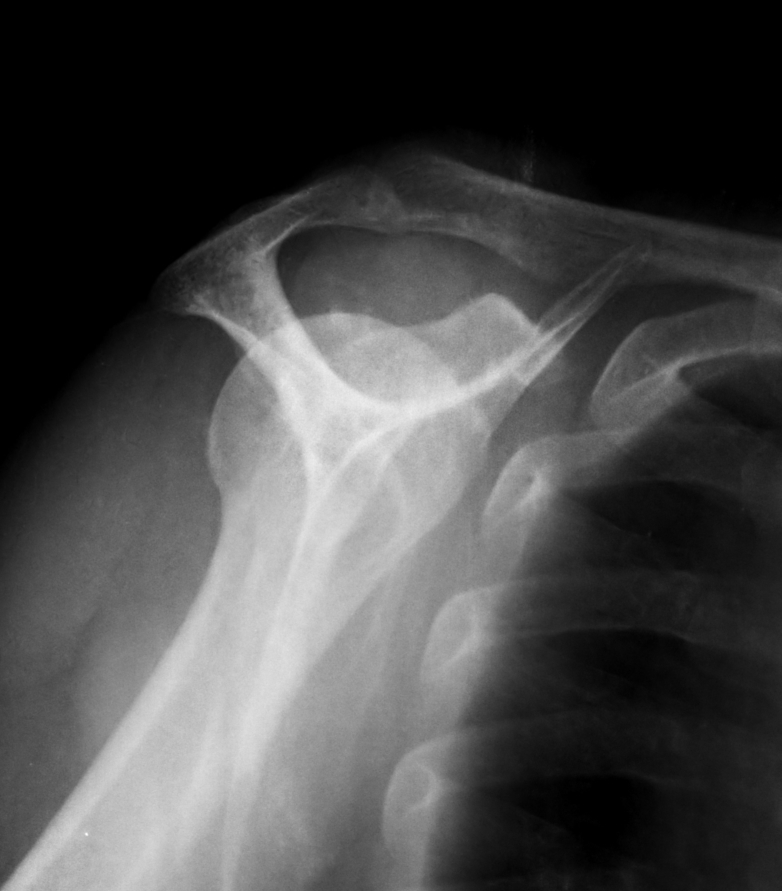

´Ü¼ø¹æ»ç¼±°Ë»ç

type II °ßºÀ(°íÂû »çÁø)